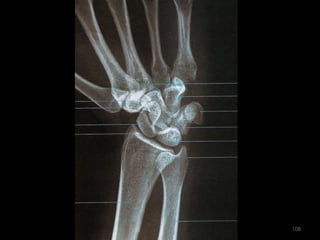

Incidência AP e PA do Punho88

89

90